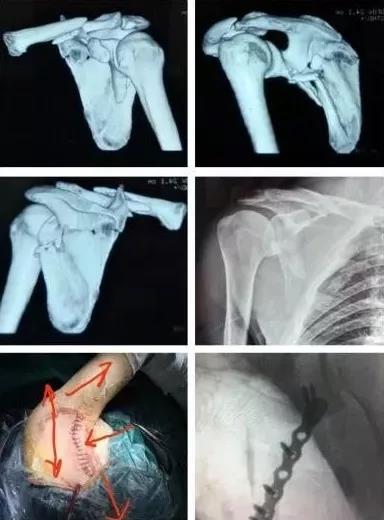

2)肩胛骨骨折

在2周之后手术,困难程度翻番。